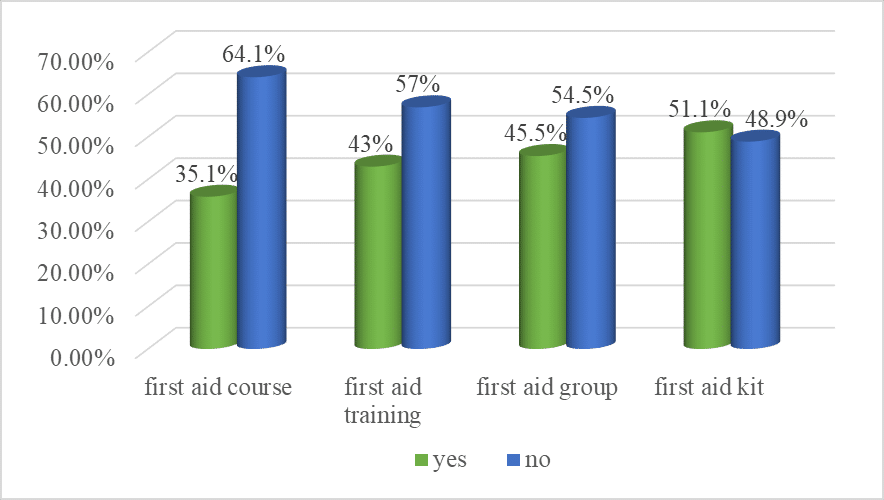

Public Health | Oct 17, 2024

Knowledge, Attitudes, and Associated Factors Towards First Aid Among Secondary School Teachers Working in Governmental Schools of Harari Regional State, Eastern Ethiopia

Background: Secondary school teachers are primarily responsible for keeping the welfare of their students, and they are the first responsible...Read More